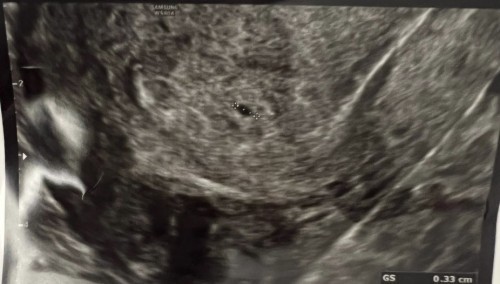

Hi everyone! How does your baby look like at 5-6 weeks on your first scan? I went to a private gynae for an ultrasound as my clearblue digital states at 3+ Gynae confirms i’m pregnant but not sure if that’s the baby and told me to come back in another week. Had a chemical pregnancy just last month, so am abit anxious to know. TIA! #firstbaby #pleasehelp

Read moremy gestational sac was 0.33cm at 5 weeks. and can see yolk sac too. but not sure how it look like as doc nv show me the scan image. but my 6 weeks 2 days scan.. it is a clear gestational sac and can see yolk sac and fetal pole. also heartbeat can be seen.

no it doesn’t look like this.. it’s a bigger circle with yolk sac. is it because yours is only 3 weeks ?